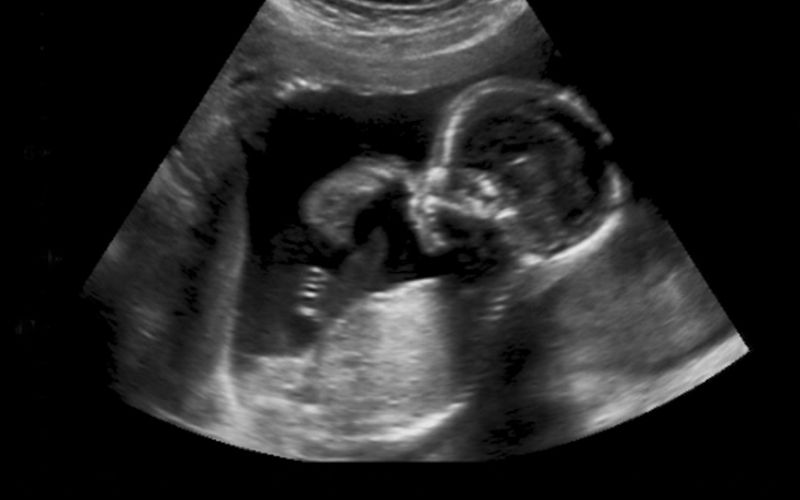

Siêu âm 2D còn được gọi là siêu âm 2 chiều. Đây là phương pháp sử dụng sóng siêu âm tần số cao, phát ra từ đầu dò để ghi lại hình ảnh thai nhi trong bụng mẹ. Qua đó, bác sĩ có thể quan sát và thu thập được các chỉ số cần thiết nhằm đánh giá tình trạng phát triển của thai.

Hình ảnh siêu âm 2D thường là ảnh đen trắng, hiển thị theo chế độ mặt phẳng. Tùy vào từng vị trí của thai, bác sĩ còn có thể xác định vị trí thai làm tổ đúng hay không, kích thước tử cung, túi thai và số lượng thai bao nhiêu,... Ngoài ra, phương pháp này còn có thể phát hiện được những bất thường của thai nhi, giúp mẹ có những hướng xử lý can thiệp kịp thời.

Sau đó, bác sĩ sẽ tiến hành dịch chuyển đầu dò tại nhiều vị trí trên mặt bụng để thu hình ảnh thai nhi. Trên màn hình máy tính siêu âm sẽ hiển thị các chỉ số quan trọng. Từ đó, bác sĩ sẽ phân tích cho cha mẹ biết để nắm rõ hơn về tình trạng sức khỏe thai nhi.

Hình ảnh đen trắng và hình phẳng đáy đôi khi chất lượng ảnh thu được bị mờ: Điều này khiến mẹ chỉ nhìn được một góc độ nhất định của em bé, khó quan sát toàn bộ hình thái cơ thể và biểu cảm trên gương mặt con.